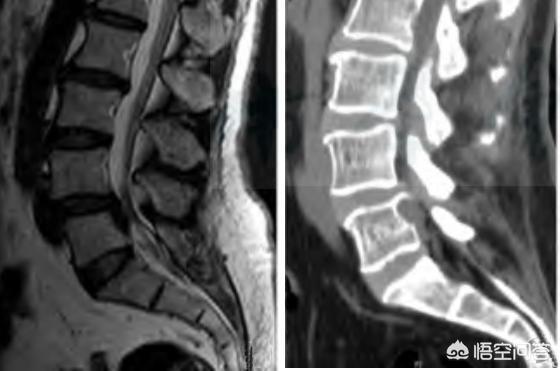

La sténose rachidienne lombaire est un état dans lequel le canal rachidien lombaire ou le foramen intervertébral est rétréci, comprimant la cauda equina ou les racines nerveuses, et ses principales manifestations sont la lombalgie et la sciatique, souvent accompagnées de symptômes de claudication intermittente. Le diamètre central du canal rachidien ≤10mm est une sténose absolue, 10~13mm est une sténose relative, et les diamètres antérieur et postérieur de la fosse saphène latérale de 3mm ou moins sont une sténose.

Le canal rachidien est un tube osseux et fibreux formé par les foramina de toutes les vertèbres, qui contient la moelle épinière, la membrane dorsale et le tissu adipeux. Il se compose de l'arrière des vertèbres, du bord postérieur des disques intervertébraux et du ligament longitudinal postérieur à l'avant, de la plaque arquée, du ligament flavum et des articulations synoviales articulaires à l'arrière, ainsi que des racines vertébrales et des foramina intervertébraux des deux côtés, les racines nerveuses sortant des foramina intervertébraux. Le canal rachidien est le plus étroit entre la quatrième et la sixième vertèbre thoracique, et plus petit entre la septième vertèbre cervicale et la quatrième vertèbre lombaire. La sténose rachidienne est causée par des facteurs congénitaux et des facteurs acquis tels que la hernie discale lombaire, l'hyperplasie du corps vertébral, le spondylolisthésis et l'hypertrophie du ligament longitudinal postérieur et du ligamentum flavum.En bref, les lésions des structures tissulaires adjacentes qui composent le canal rachidienSténose rachidienne causée par, etc. La sténose spinale se trouve dans les segments cervical, thoracique et lombaire, et la sténose spinale lombaire, par exemple, se manifeste cliniquement comme suit1. douleur, faiblesse musculaire, douleurs diverses, telles que douleur, engourdissement, gonflement, douleur ressemblant à un écoulement et douleur brûlante ; 2. compression de la cauda equina, dysfonctionnement du transit intestinal, engourdissement du périnée ; 3. claudication intermittente (manifestations caractéristiques, apparaissant lors de la marche et s'améliorant après avoir été debout ou accroupi et s'être reposé).